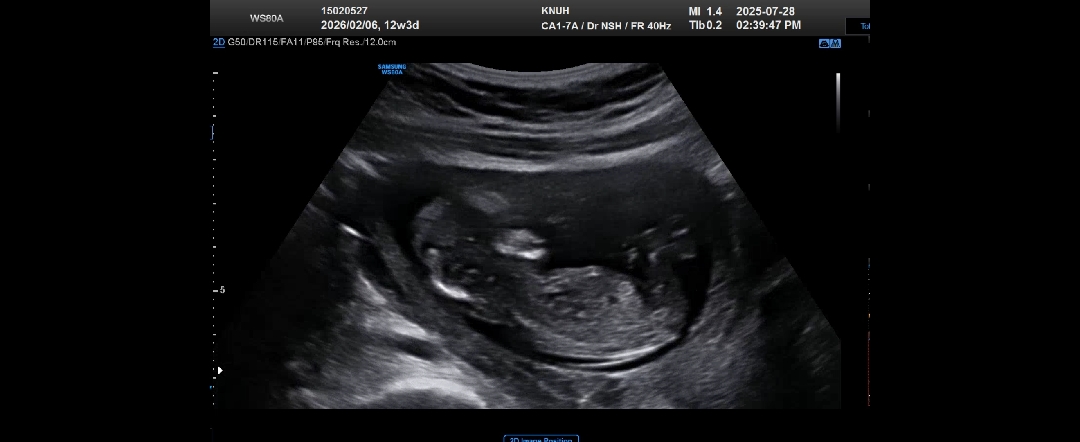

각도법 고수님들 도와주세요!!

잘 안보이려나요?ㅠㅠ 12주 3일인데 봐도봐도 모르겟어요..